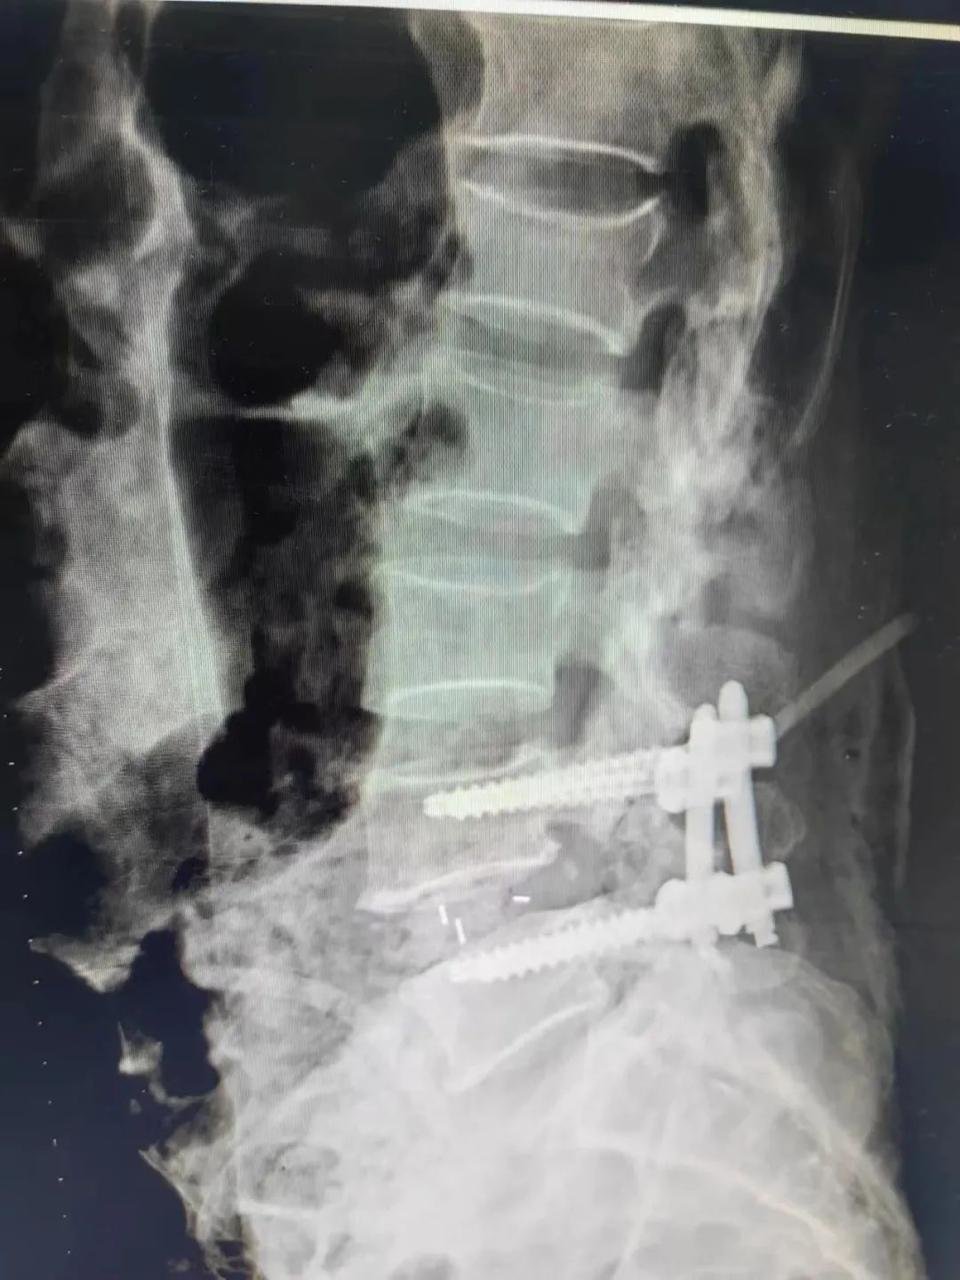

骨科二十二病室(脊柱外科)主任陈立带领团队详细检查评估后,5月19日,顺利为杨阿姨进行后路腰4-5椎弓根螺钉内固定+椎间融合器植入植骨融合手术。